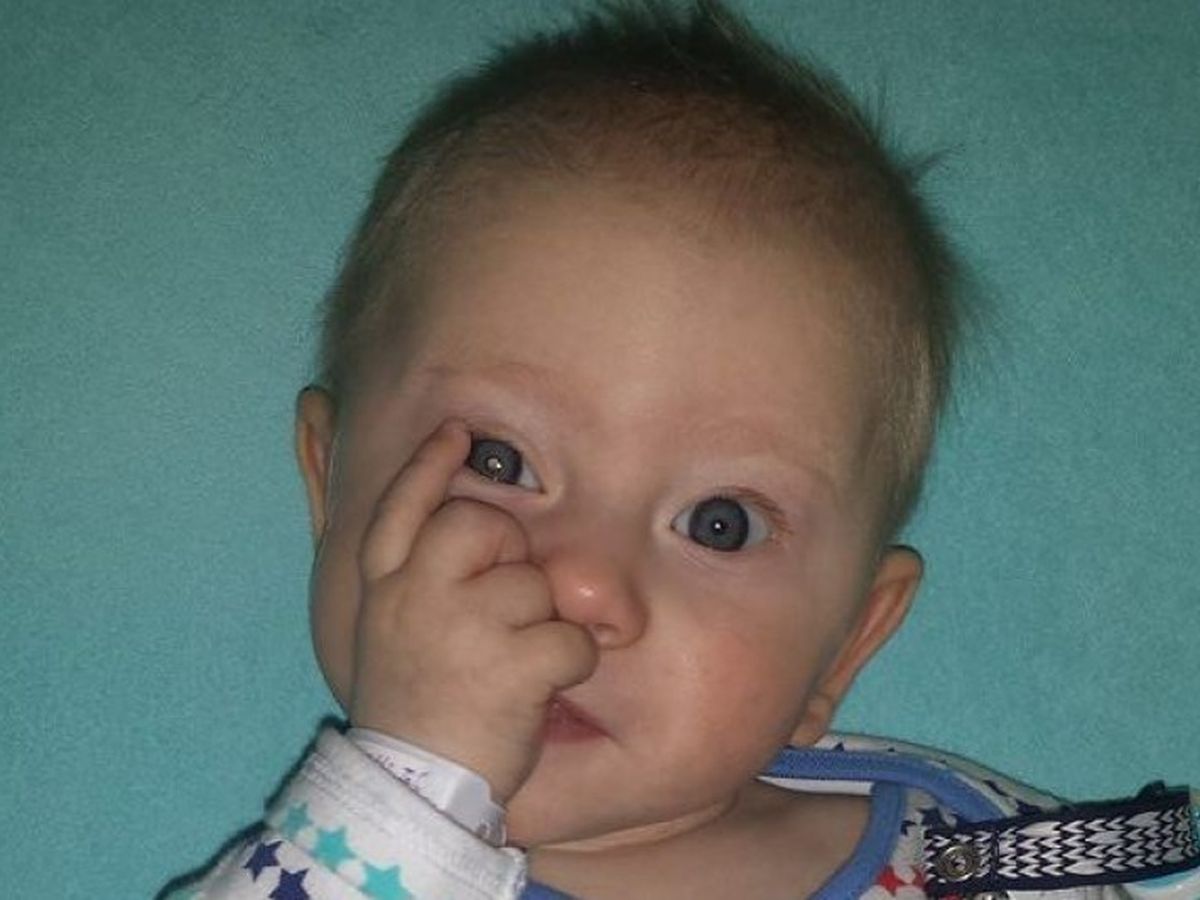

Tymon is my 5 month old godson, who in March 2016 was diagnosed with a rare, aggressive cancer of the eye -RETINOBLASTOMA. If retinoblastoma tumors are not treated quickly, they lead to vision loss, and can spread to the brain.

The tumour within Tymon's eye can be seen as the white glare in his right pupil.

The tumour within Tymon's eye can be seen as the white glare in his right pupil.

The tumour within Tymon's eye can be seen as the white glare in his right pupil. Tymon with his mom